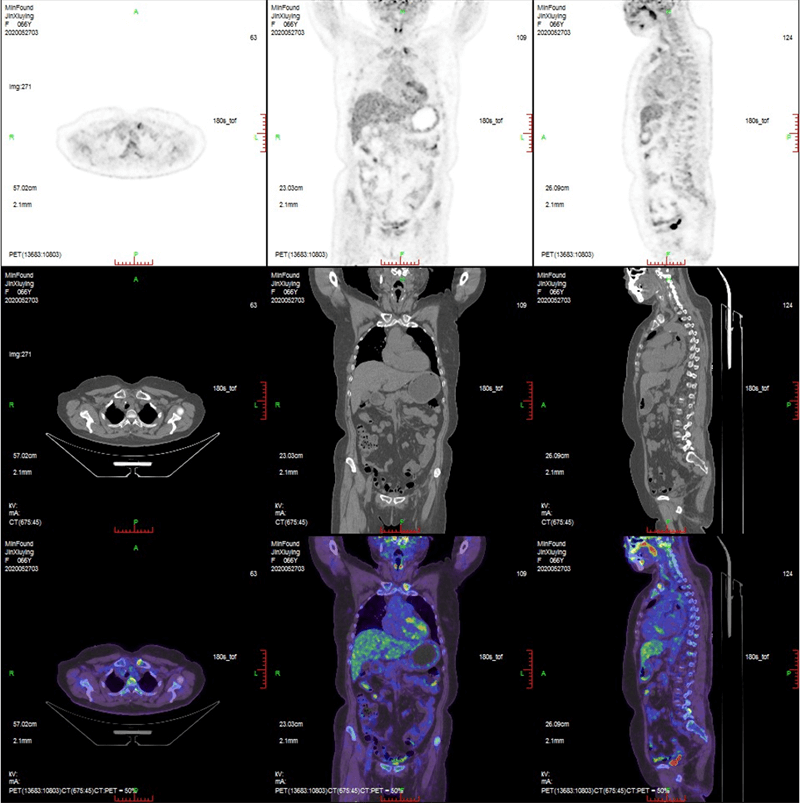

臨床畫廊